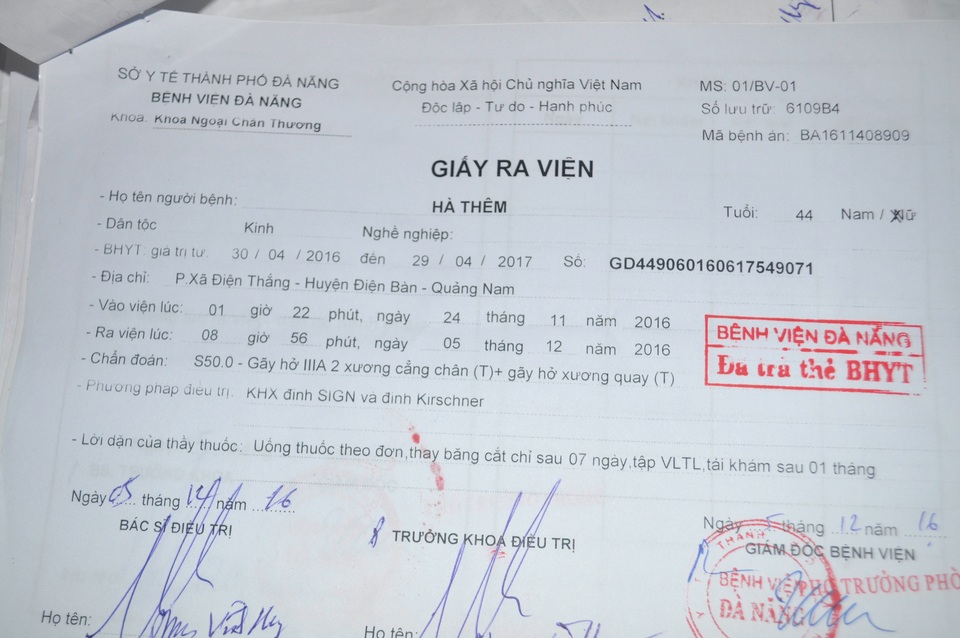

Nhưng bi kịch vẫn chưa hồi kết thúc khi cách đây gần một tháng anh được người thân chở đi trên đường thì va chạm với xe máy của một thanh niên say xỉn. Sau tai nạn, anh nằm liệt một chỗ, mọi sinh hoạt cá nhân đều phải nhờ vợ, mẹ già và những người hàng xóm tốt bụng xung quanh. Một chân bị thoái hóa xương đùi ngày càng trầm trọng, nay lại thêm gãy xương cổ tay và gãy xương ống chân cần phải phẫu thuật nếu không anh có thể vĩnh viễn mất đi hai chân của mình.

Chi phí phẫu thuật lên đến 80 triệu đồng; đây là con số quá lớn đối với gia đình thuộc diện khó khăn; trong khi đó vợ anh đang còn phải chạy ăn từng bữa cho gia đình, tiền thuốc men, tiền nợ nần sau lần anh nhập viện, lãi ngân hàng từ số tiền vợ chồng vay làm nhà sau hai lần bị bão đánh sập năm 2006 và 2013...

Không kìm được lòng, chị Nga nức nở khiến chúng tôi cũng thấy xót xa, chị tâm sự: “Anh đau và khó chịu lắm, nhiều đêm ảnh trằn trọc không ngủ được vì hai chân tê nhức nhưng cũng cố chịu đựng vì sợ vợ con lo lắng. Bác sĩ bảo chỉ có phẫu thuật mới hy vọng giữ lại đôi chân nhưng 80 triệu là con số quá lớn với gia đình. Thương anh lắm nhưng tôi cũng đành bất lực, nợ cũ cũng chưa trả xong, biết xoay sở ở đâu bây giờ”.